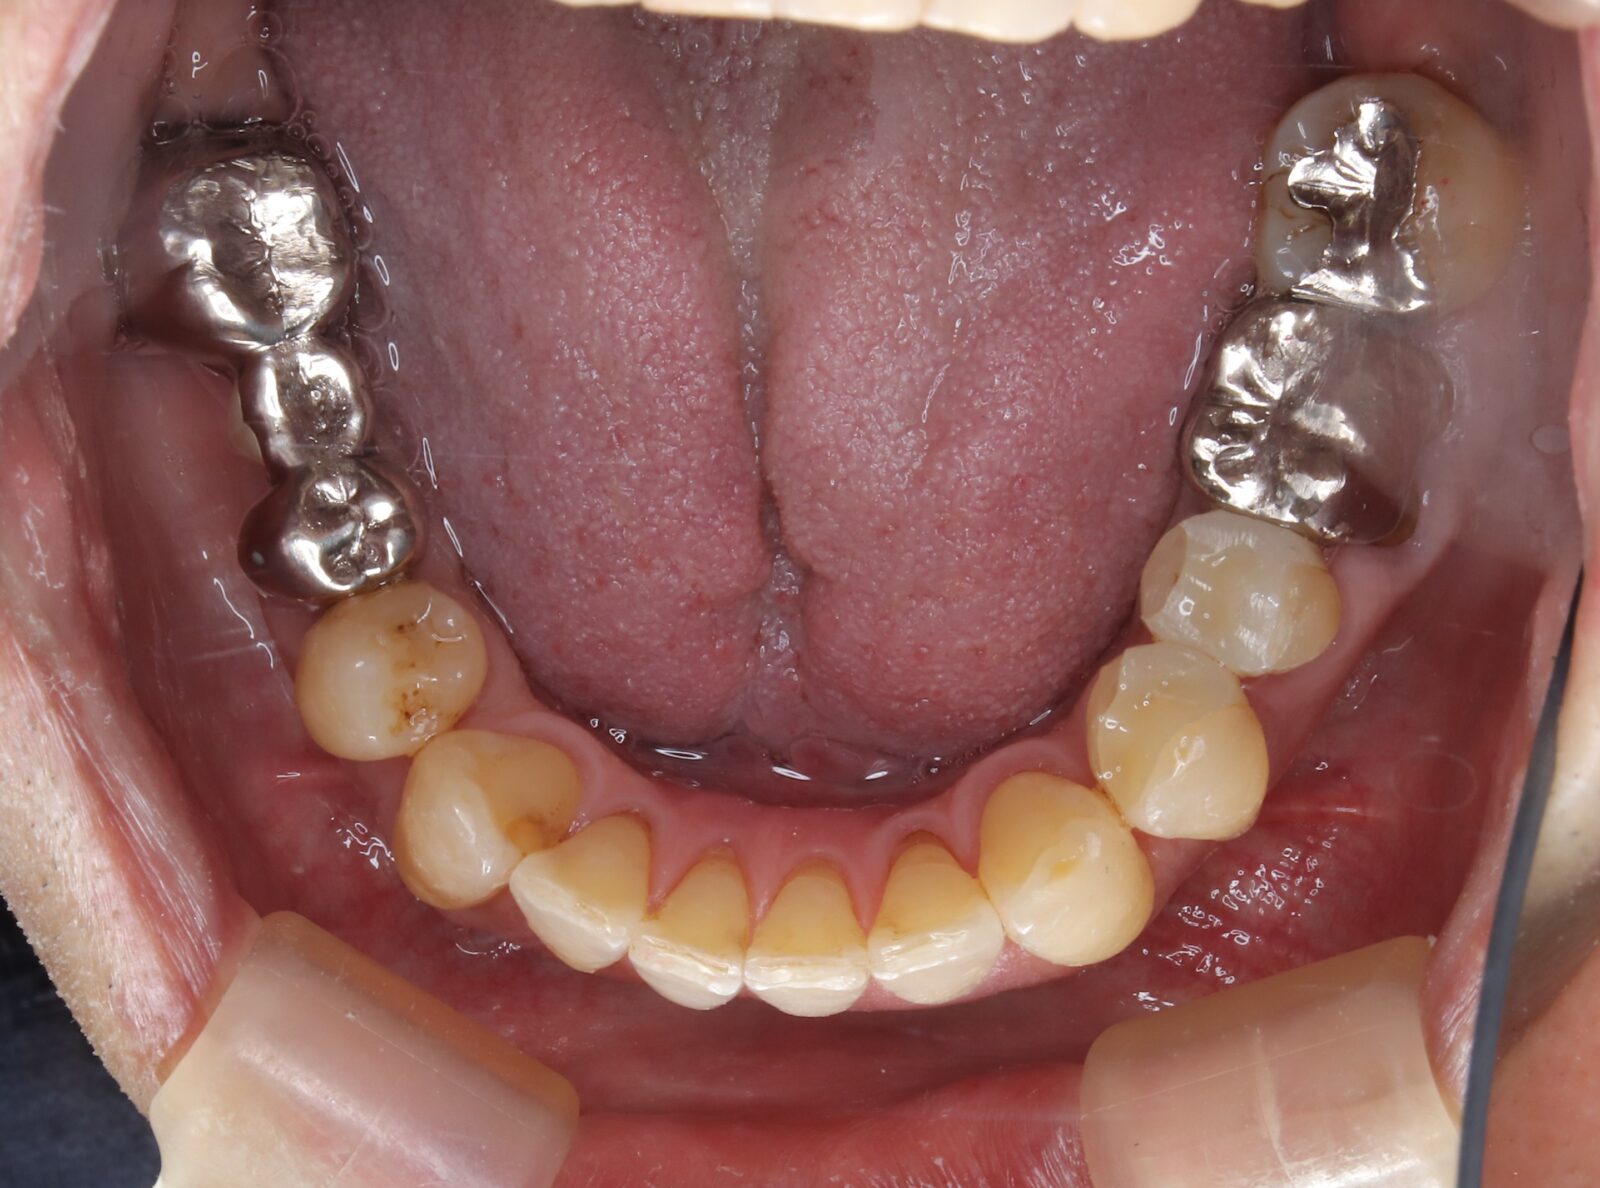

矯正と補綴が必要で実施した症例

左側に隙間。歯の数が少ない。もともと2番と7番がない。(先天欠如)歯の数が少ないため上顎のアーチ全体が小さい。歯槽骨の幅も狭く、歯肉も薄い。骨質も弱かった。

上顎左右2番と6番が先天欠如。下顎左右1番も先天欠如でもともとブリッジが装着されていた。

左右非対称なすきっ歯。上顎の前歯がないので左側の隙間を左右2番相当部に集めた。

上下の前歯が反対の噛み合わせ(受け口)で、干渉しているためうまく閉じることができず、奥歯は左右同時に噛めないので、どこかにずらさないと口を閉じられない。

左右の歯を同時に合わせることができず、どこで噛んだら良いかわからない噛み合わせでした。

小臼歯部は噛み合うことがない側方の開口状態。矯正と補綴が必要なケース。 主訴は顎の不調と歯軋り、夜間の食いしばり。

マルチブラケットとインビザラインを併用し、クラウンとブリッジを装着しました。

上顎左右2番は、歯が入るスペースを作り、ブリッジを装着しました。

他の歯医者で何軒も断られていました。 骨の幅がうすくインプラントはできない。骨の質も柔らかい。PCR検査の結果も歯周病ハイリスク患者でした。

歯の位置は、本人の顎が安定する場所を探して着地した。 左右で噛み合わせが非対称で、理想的な歯のポジションを獲得できなかったものの、左右同時に噛むことができるようになった。

顎関節の症状も落ち着いて、開口障害や、顎の痛みは無くなった。

矯正治療はどの装置を選択しても歯周病のリスクを高めてしまう。

これ以上の歯の移動が歯周病と骨質、骨の代謝のバランスの兼ね合いで困難であると判断し、ここが着地点とした。